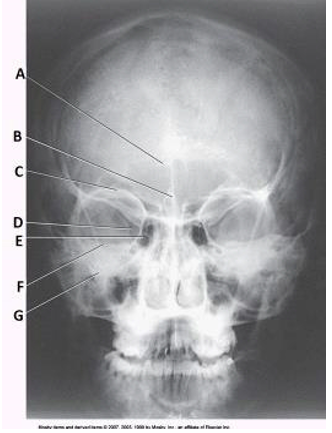

Name the structures in the image below.

A

C

E

F

A: Frontal sinuses

C: Superior orbital margin

E: Ethmoid sinuses

F: Petrous ridge